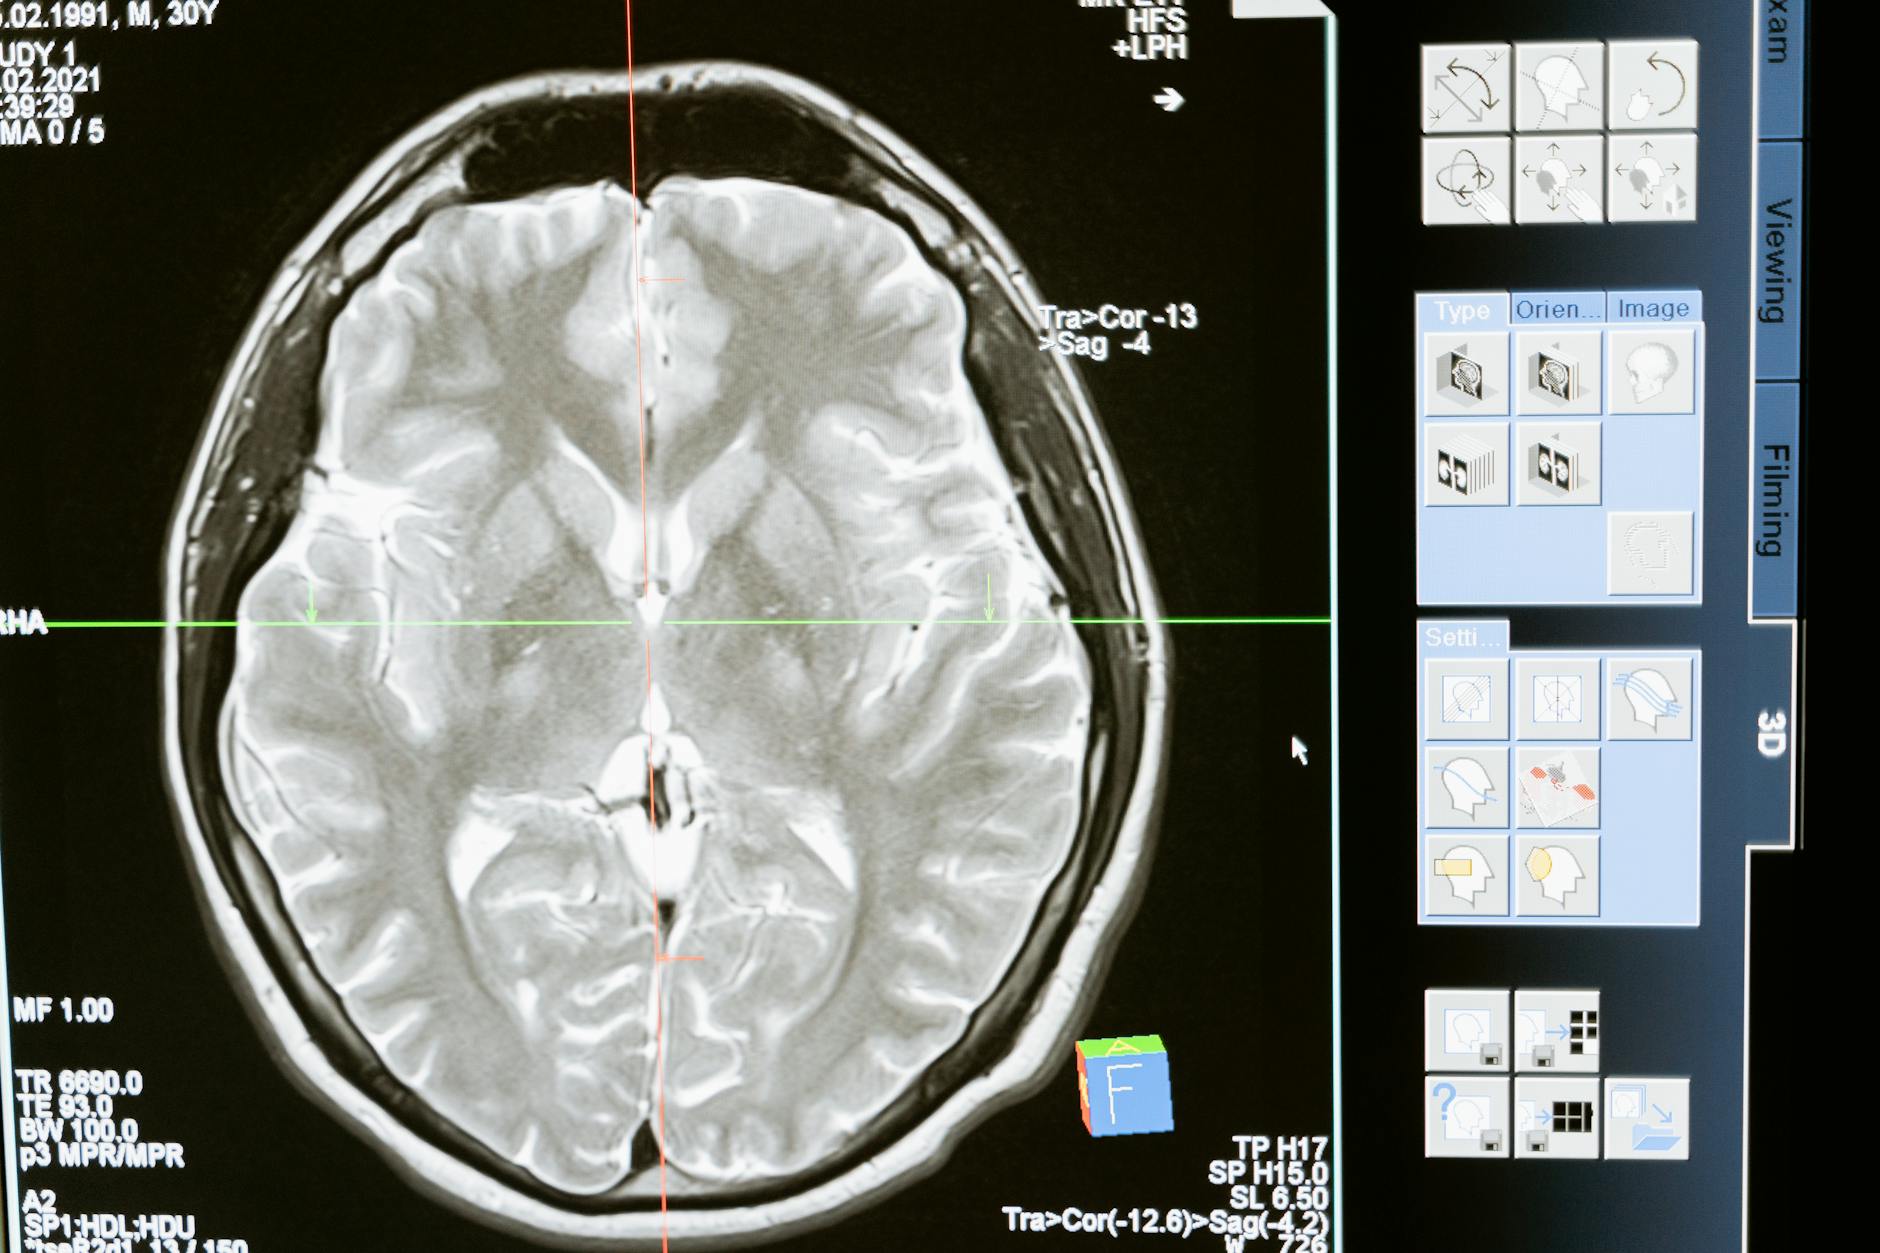

GE HealthCare anunció que el primer paciente ha recibido la dosis en LUMINA, un ensayo internacional multicéntrico de Fase 2/3 del mangaciclanol —agente de contraste para resonancia magnética basado en manganeso— en Mayo Clinic, Rochester, Minnesota. Si supera la barrera regulatoria, el mangaciclanol podría ofrecer una alternativa, o incluso reemplazar, a los agentes basados en gadolinio, estándar actual en RM con contraste.

Los estudios preclínicos y la Fase 1 del mangaciclanol indican una relaxividad comparable al gadobutrol, uno de los agentes macrocíclicos más utilizados, con calidad de imagen diagnóstica reportada como similar en las primeras adquisiciones. En la práctica: la señal de contraste y la conspicuidad lesional se mueven en la misma ventana familiar para el radiólogo, sin necesidad de protocolos radicalmente distintos.

LUMINA es un ensayo internacional multicéntrico de Fase 2/3 diseñado para sustentar la solicitud de aprobación ante la FDA y otras agencias. La primera dosis se administró el 23 de abril de 2026 en Mayo Clinic. El ensayo evalúa el desempeño diagnóstico del mangaciclanol en poblaciones adulta y pediátrica, con criterios de valoración centrados en la detección y caracterización de lesiones con vascularización anormal en SNC y en otras regiones corporales.